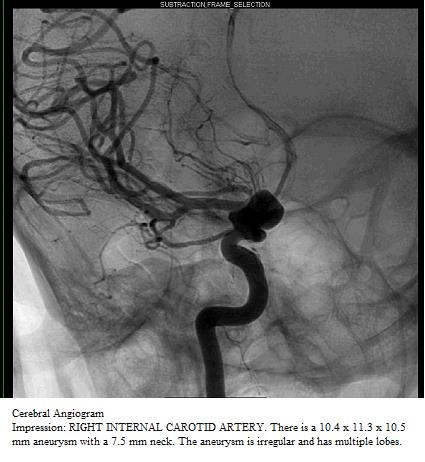

Case Presentation: A 28 year-old woman with AIDS and a CD4 count of 178 cells/mm3, not on antiretroviral therapy, presented with odynophagia for 2 weeks as well as increased swelling in her neck and inguinal area. She denied any neurological symptoms. On physical examination, the patient had extensive cervical lymphadenopathy with no other significant findings. EGD revealed esophageal candidiasis and HSV esophagitis. Fluconazole, acyclovir, dolutegravir, and emtricitabine/tenofovir were started. CT neck with contrast to evaluate the lymphadenopathy incidentally showed an enlargement of the right internal carotid artery with suspicion for aneurysm. MRA confirmed a 17 mm x 19 mm x 19 mm right supraclinoid internal carotid artery aneurysm extending to the origin of the right ophthalmic artery. The sizable intracranial aneurysm prompted immediate angiography that revealed a right ophthalmic and left anterior cerebral artery aneurysm. She was transferred to the neurosurgical service with plans to place a pipeline stent in the right ophthalmic aneurysm. The procedure was postponed due to MRSA bacteremia and the patient was lost to follow-up after discharge.